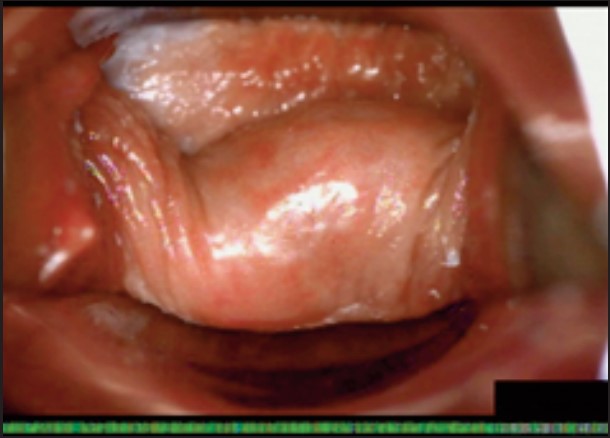

Під час спостереження до та після процедури, через 16 і 36 діб було зроблено вагінальні фотографії за допомогою Tele-Cervico (цервікографія) та виконано порівняння результатів до /після.

У пацієнток 1, 2 і 3 вагінальні складки утворилися та увиразнилися помітніше та сильніше, ніж вони були до лікування, ми оцінили цей клінічний результат після 1-го сеансу (через 16 діб). На нашу думку, такі виразні складки свідчать про підтяжку слизової оболонки піхви, що добре впливає на ущільнення піхви та проблему нетримання сечі. Через 36 діб після процедури ми спостерігали, що зруйнована анатомічна структура піхви відновила Н-подібну форму, тобто стала набагато здоровішою. Зокрема, у пацієнтки 4 структура піхви була цілковито зруйнована, стінки піхви обвисали через втрату еластичності. Однак через 36 днів після процедури структура піхви повністю відновила здорову Н-подібну форму [Див. Малюнок 3].

Пацієнтка №2

До

Після 36 діб

| Вік | 38 |

| Пологи | Природні. 1 дівчинка. |

| Лікування | 2 сеанси / 1 місяць |

| Огляд | 36 діб |

| Протокол | 1 сеанс – 440 імпульсів 2 сеанс – 200 імпульсів |

| Результати | √ Відновлено H-подібну структуру √ Збільшено складки √ Дещо зменшилися симптоми SUI |